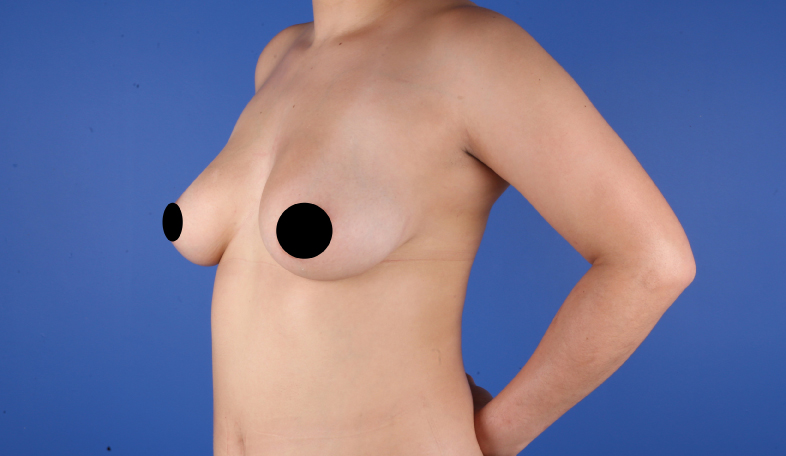

Es una ayuda diagnóstica complementaria que se utiliza para capturar imágenes de cualquier parte del cuerpo, aplicando técnicas que permitan obtener fotografías proporcionales, detalladas y nítidas; empleadas para medir, trazar, predeterminar y planear un proceso quirúrgico.

Es utilizada para crear imágenes del cuerpo humano, o partes de él, con propósitos clínicos que buscan revelar, diagnosticar y planear un tratamiento médico.